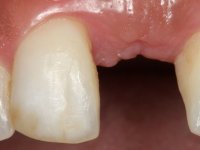

A paciente de sexo feminino de 28 anos de idade perdeu por traumatismo o incisivo central superior esquerdo. Preocupada com o seu sorriso, a paciente apareceu no consultório querendo alinhar os dentes antero-superiores para obter uma aparência mais natural. Sendo fumadora a paciente não apresentava problemas médicos dignos de registo.

A paciente apresenta um desvio da linha média superior de 6 mm para a esquerda. Resultado da ausência do incisivo central superior esquerdo, os dentes adjacentes inclinaram mesialmente para esta zona, limitando o espaço disponível para a reabilitação prostodontica. Existe uma significativa desarmonia dentária negativa no arco maxilar como resultado da ausência do 21, ausência do primeiro pre-molar com um espaço residual, significativa redução coronária do segundo pre-molar direito, migração dos dentes posteriores para os espaços não preenchidos e uma mesialização molar superior esquerda e direita com uma relação molar em Classe II. Ambos os caninos esquerdo e direito mostram uma relação Classe II na posição de inter-cuspidação máxima. A paciente apresenta uma linha de sorriso média, um biótipo gengival médio grosso, apresenta uma correcta higiene oral sem doença periodontal. Não apresenta hábitos para –funcionais. O exame radiográfico mostra uma significativa inclinação dos eixos dos dentes 11 e 22 com espaço entre a porção apical das raízes. A análise cefalométrica foi feita com o intuito de explorar a hipótese de conseguir arranjar espaço para a colocação de um implante e de uma coroa no local do dente 21. Finalmente a morfologia do osso residual presente na região anterior da maxila foi avaliado com uma TAC, revelando uma perda das dimensões da parede óssea vestibular.